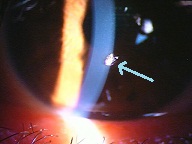

黄斑円孔の手術に関しては、?で記載しましたが、簡単におさらいすると、目の中に器械をいれて、内境界膜という網膜の表層の膜を剥離し、網膜を柔らかくします。その後、目の中に空気を入れてうつ伏せをすることで、円孔の周囲の網膜を浮力で引き寄せて、穴を閉じる。という方法です。

?手術の効果で、青や緑の網膜を中心部に引き寄せます。